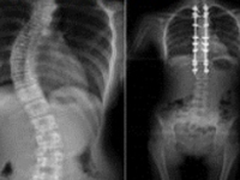

2017-04-28 关键字:导板基于患者的影像数据设计,其提高了手术的精确度,且术中不需要研磨椎板、寻找椎弓根,缩短手术时间;提高了椎弓根钉的固定强度,因此3D打印导板在治疗脊柱侧弯手术中应被广泛应用。三的部落不断累积行业经验,......